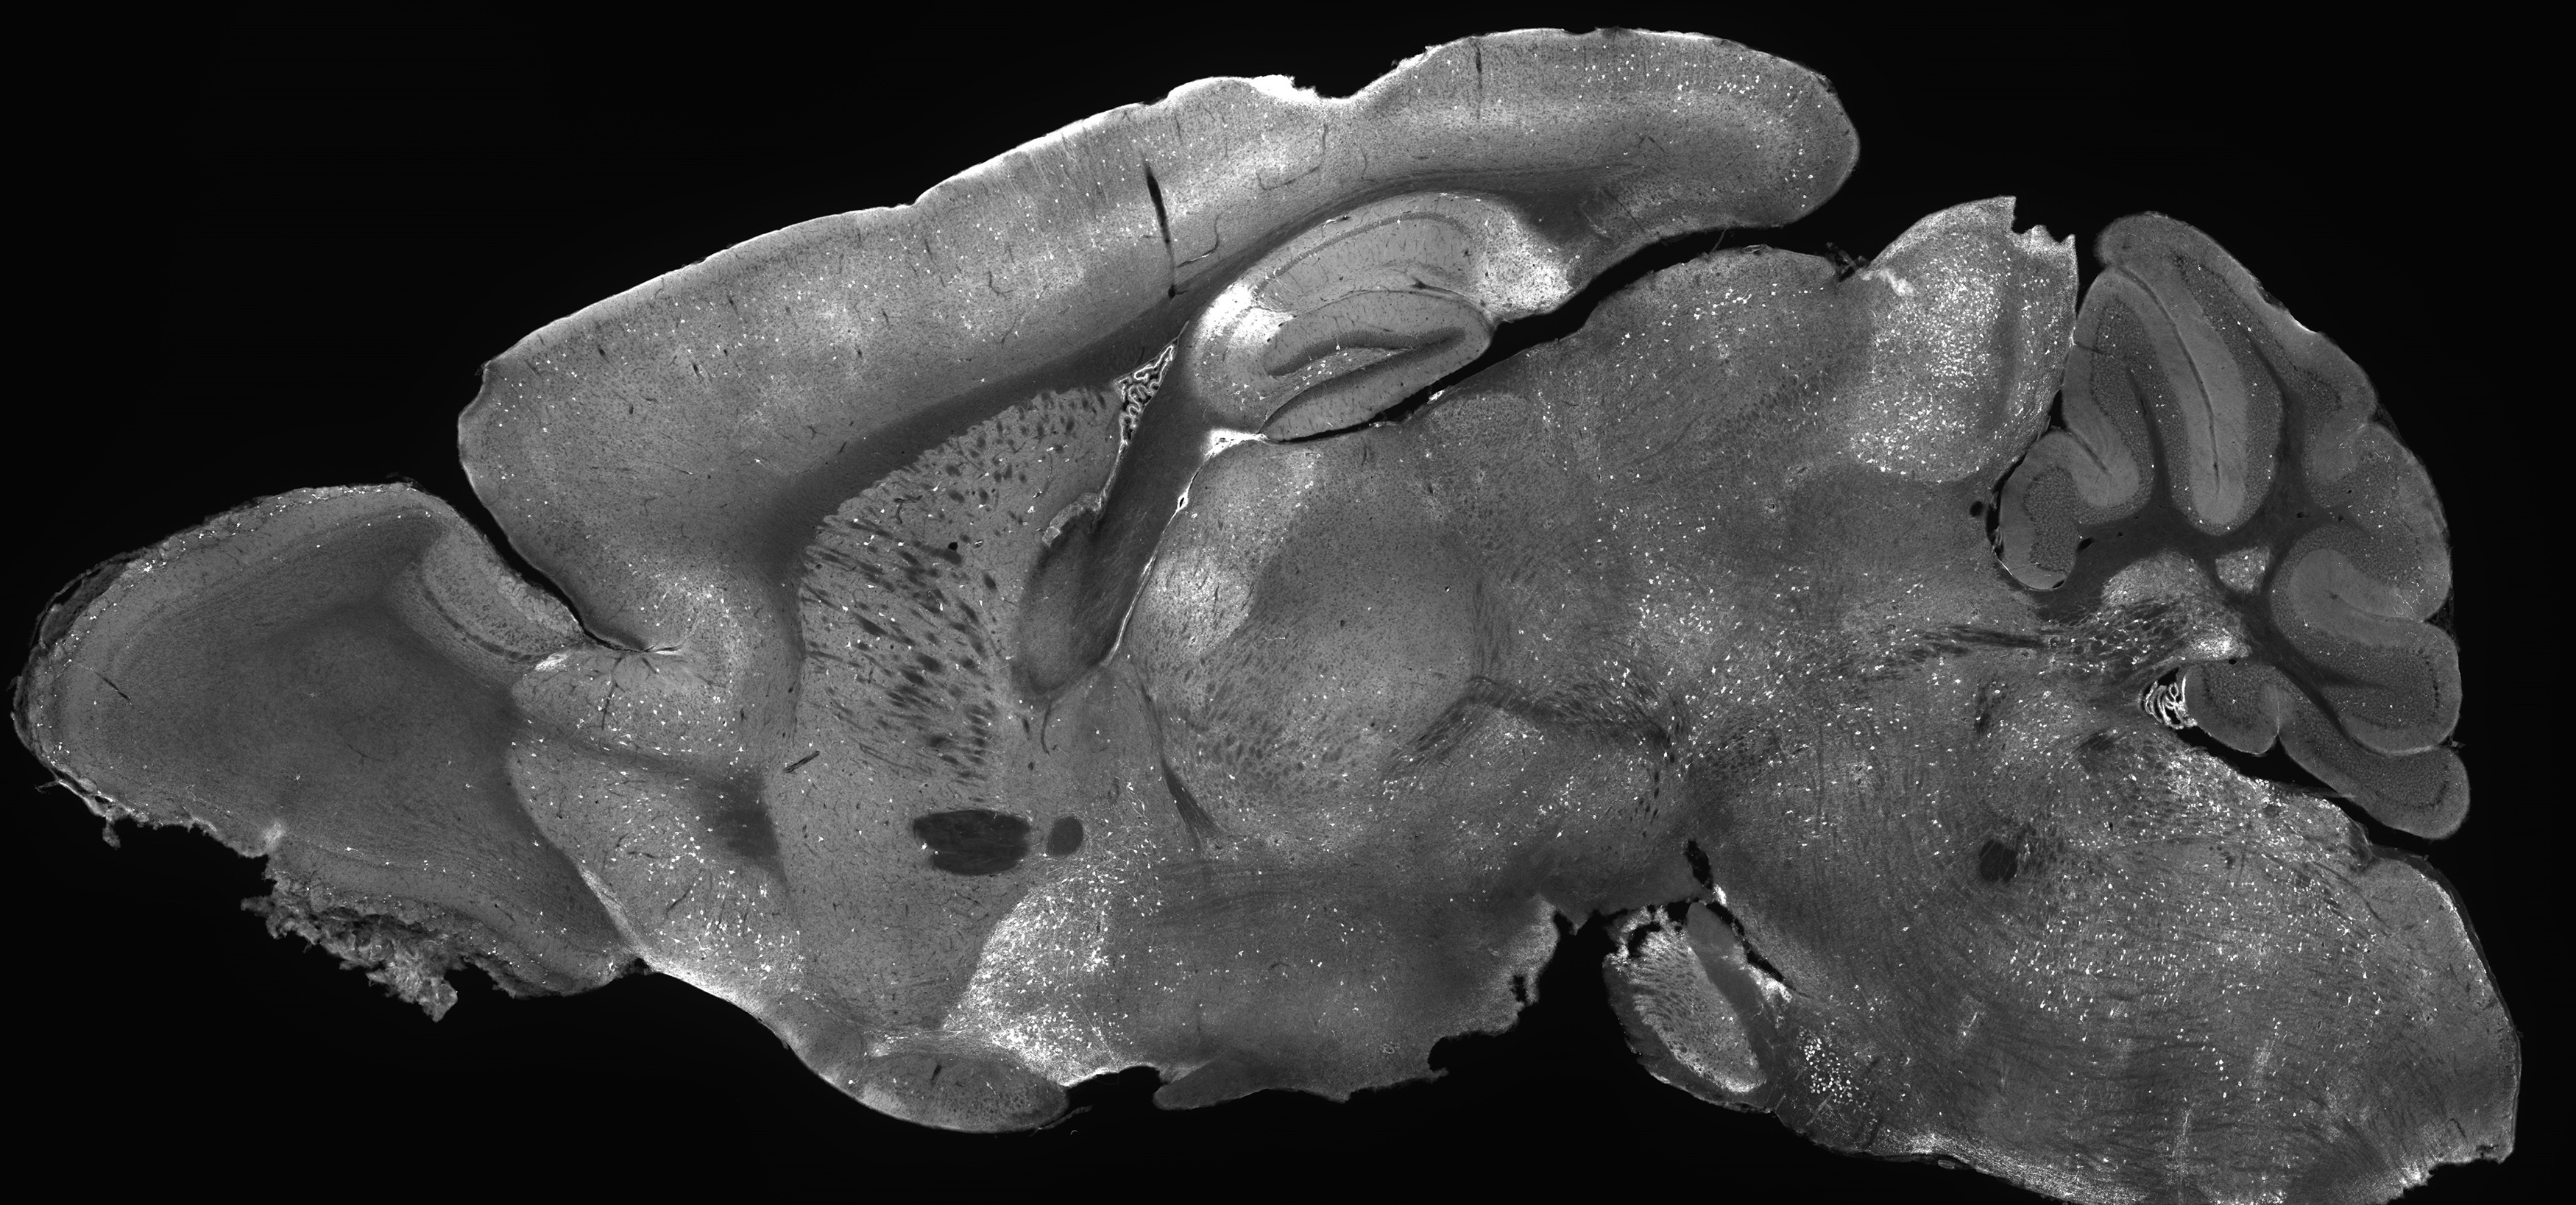

Black and white microscope image of a mouse brain slice

Mouse brain image glowing with experimental gene supplementation therapy highlighting how AAV delivers treatment across the entire brain (Photo credit: Allen Institute/Andrew Clark)